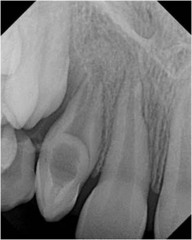

Teeth with enlarged pulp chambers causing the view small roots

Taurodontism